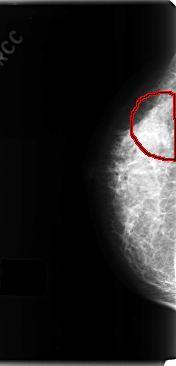

C_0198_1.RIGHT_MLO

RIGHT_CC LINES 4752 PIXELS_PER_LINE 2288 BITS_PER_PIXEL 12 RESOLUTION 50 OVERLAY

RIGHT_MLO LINES 4704 PIXELS_PER_LINE 2448 BITS_PER_PIXEL 12 RESOLUTION 50 OVERLAY

FILE: C_0198_1.RIGHT_MLO.OVERLAY

TOTAL_ABNORMALITIES 1

ABNORMALITY 1

LESION_TYPE CALCIFICATION TYPE AMORPHOUS DISTRIBUTION SEGMENTAL

ASSESSMENT 4

SUBTLETY 2

PATHOLOGY MALIGNANT

TOTAL_OUTLINES 1

BOUNDARY